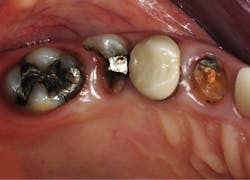

Figure 3: The second molar had about one-half of the coronal tooth structure removed and required a resin-based composite buildup. The first premolar had only a Class I defect and received a filler of bonded compomer (Dyract). The canine received a fiber-reinforced post, two pure titanium pins on the lingual (Filpins from Filhol Dental), and a resin-based composite coronal buildup.

Figure 4: These final restorations have now served for 15 years.